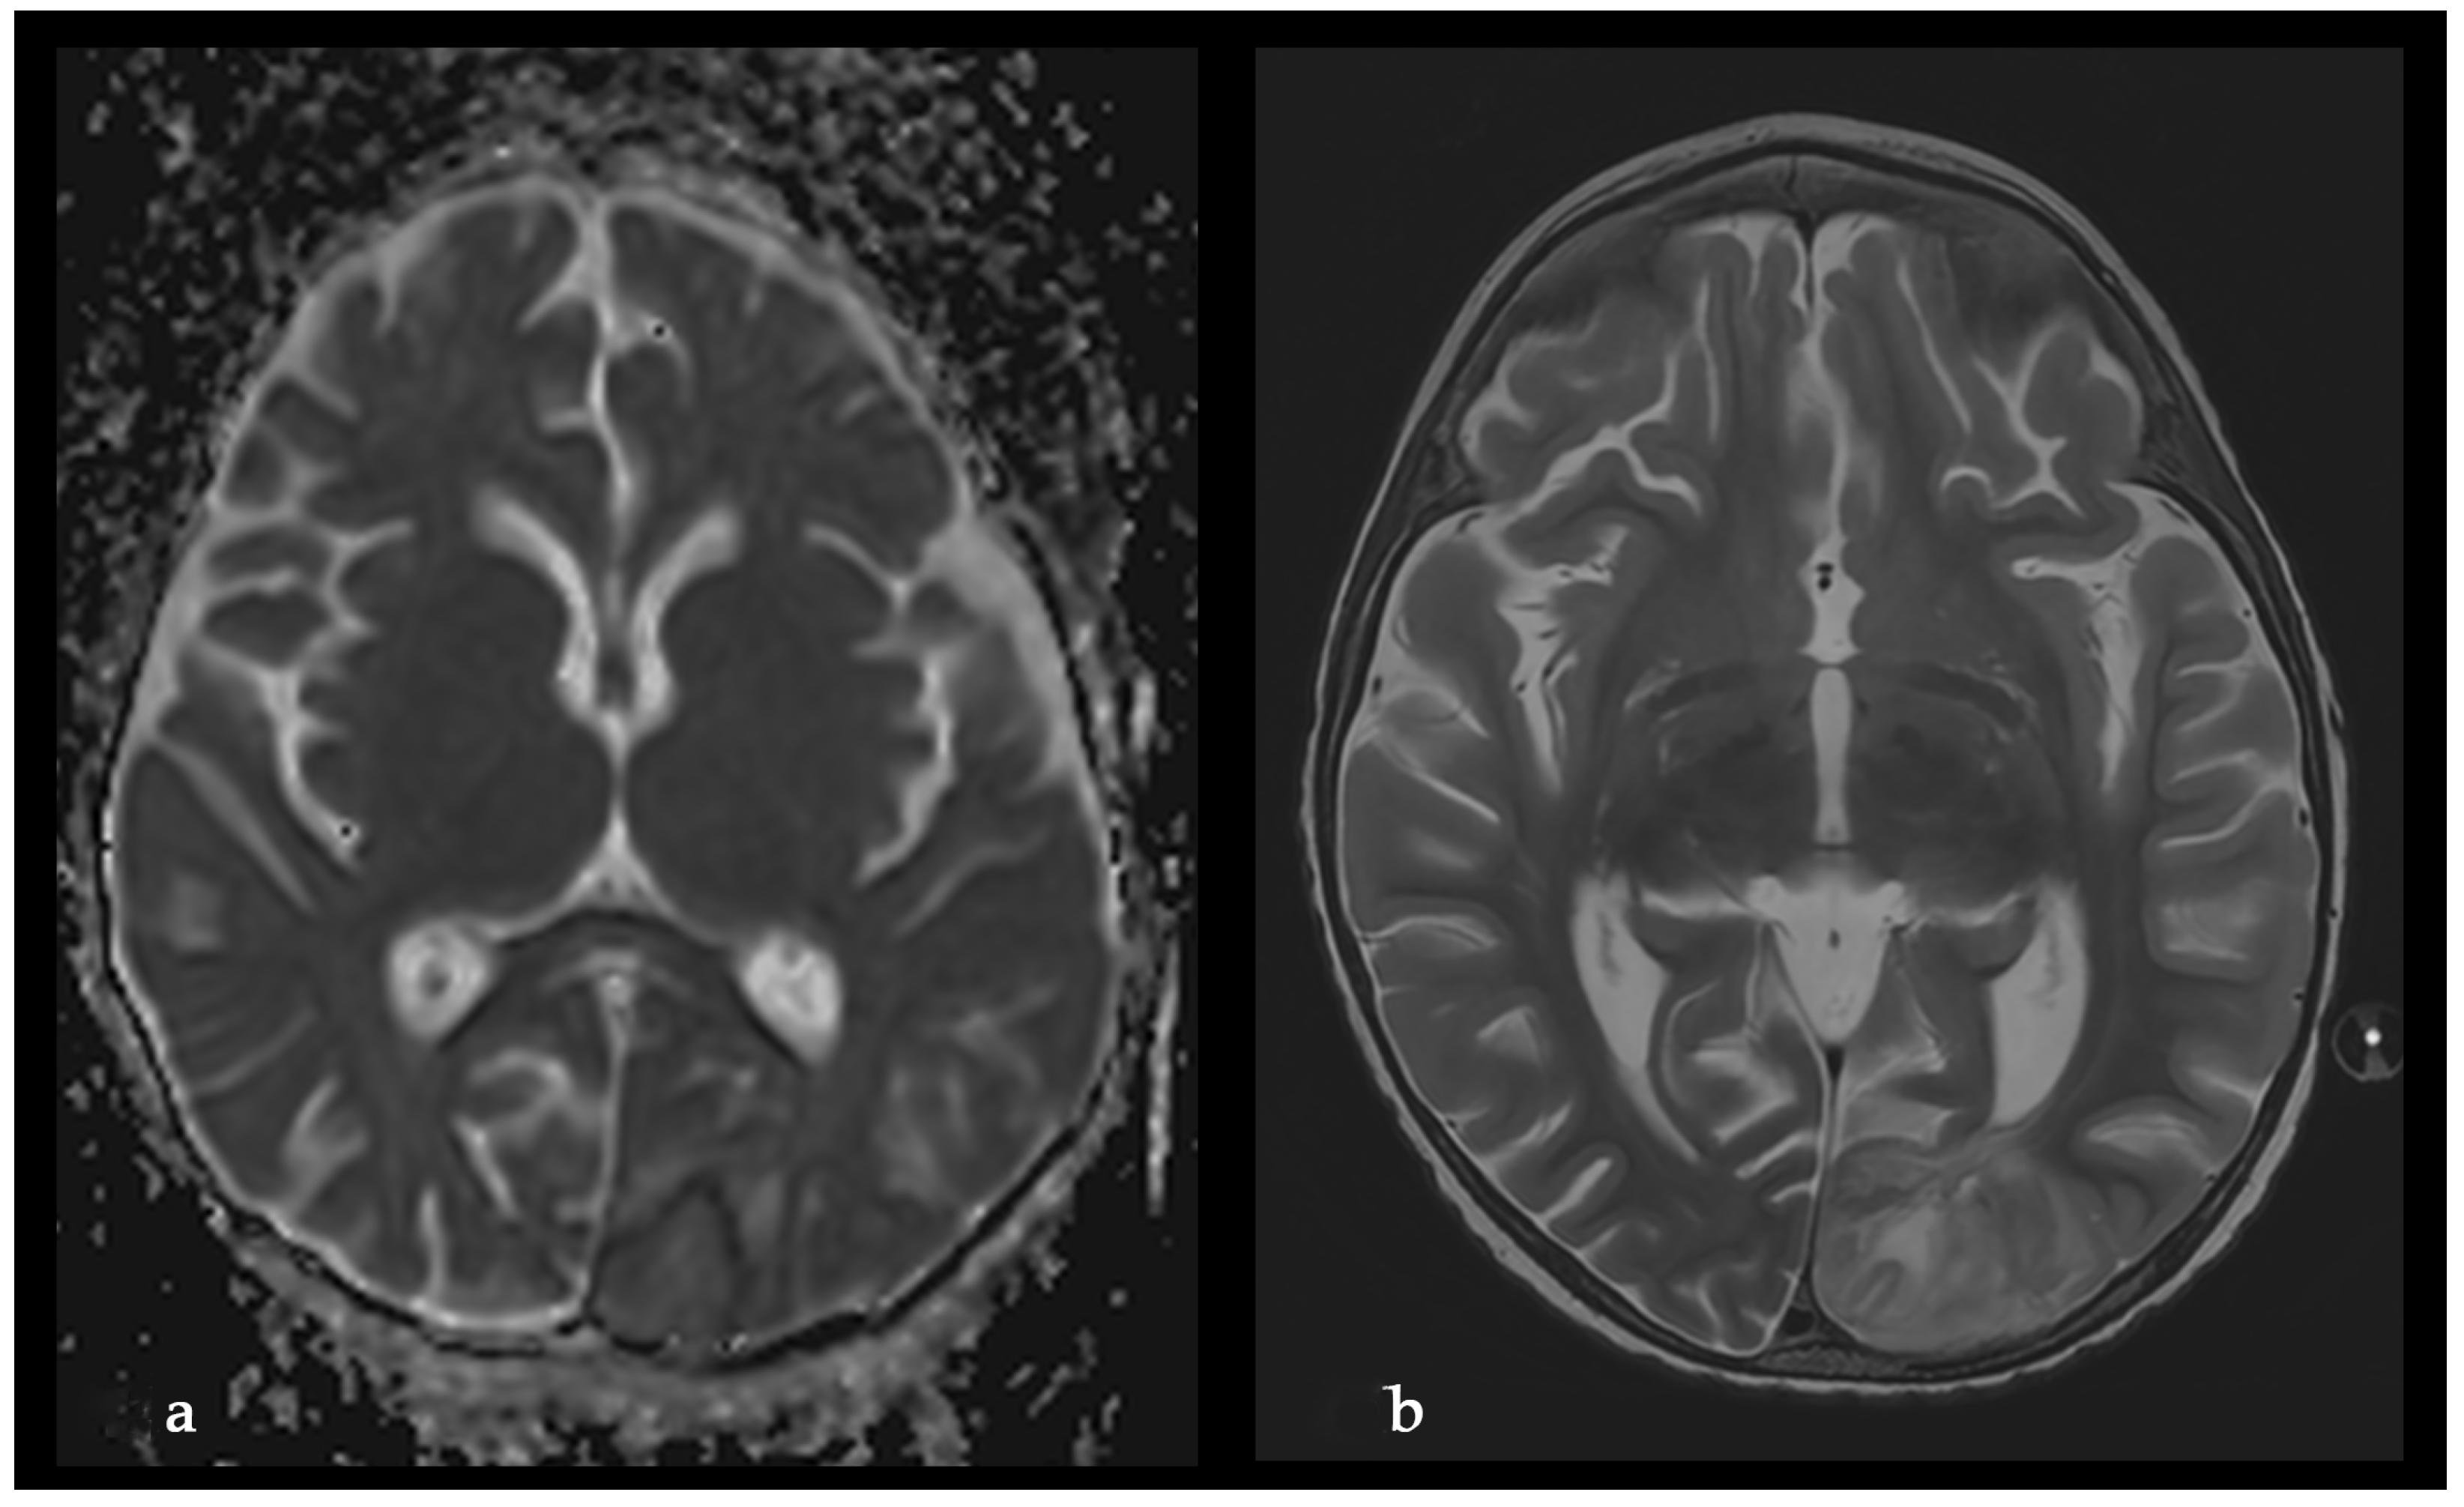

A Rare Case of Rhizomucor pusillus Infection in a 3-Year-Old Child with Acute Lymphoblastic Leukemia, Presenting with Lung and Brain Abscesses—Case Report

Pahnev, Y.; Avramova, B.; Gabrovska, N.; Dontcheva, Y.; Tacheva, G.; Minkin, K.; Kreipe, H.; Yurukova, N.; Penkov, M.; Kartulev, N.; et al. A Rare Case of Rhizomucor pusillus Infection in a 3-Year-Old Child with Acute Lymphoblastic Leukemia, Presenting with Lung and Brain Abscesses—Case Report. Infect. Dis. Rep. 2026, 18, 2. https://doi.org/10.3390/idr18010002